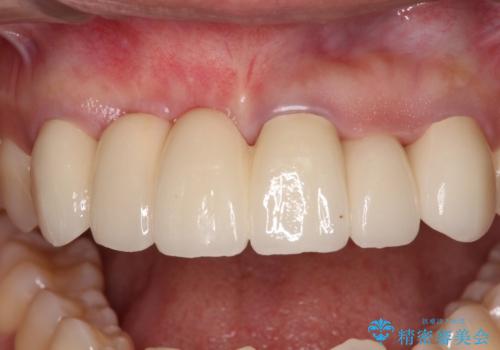

1回の歯肉移植により歯肉の厚みは大幅に改善されましたが、折角なのでもう少し大きくしたいとの要望があり、2回目の処置も行うこととしました。

厚みも高さも十分な歯肉量を獲得することができました。